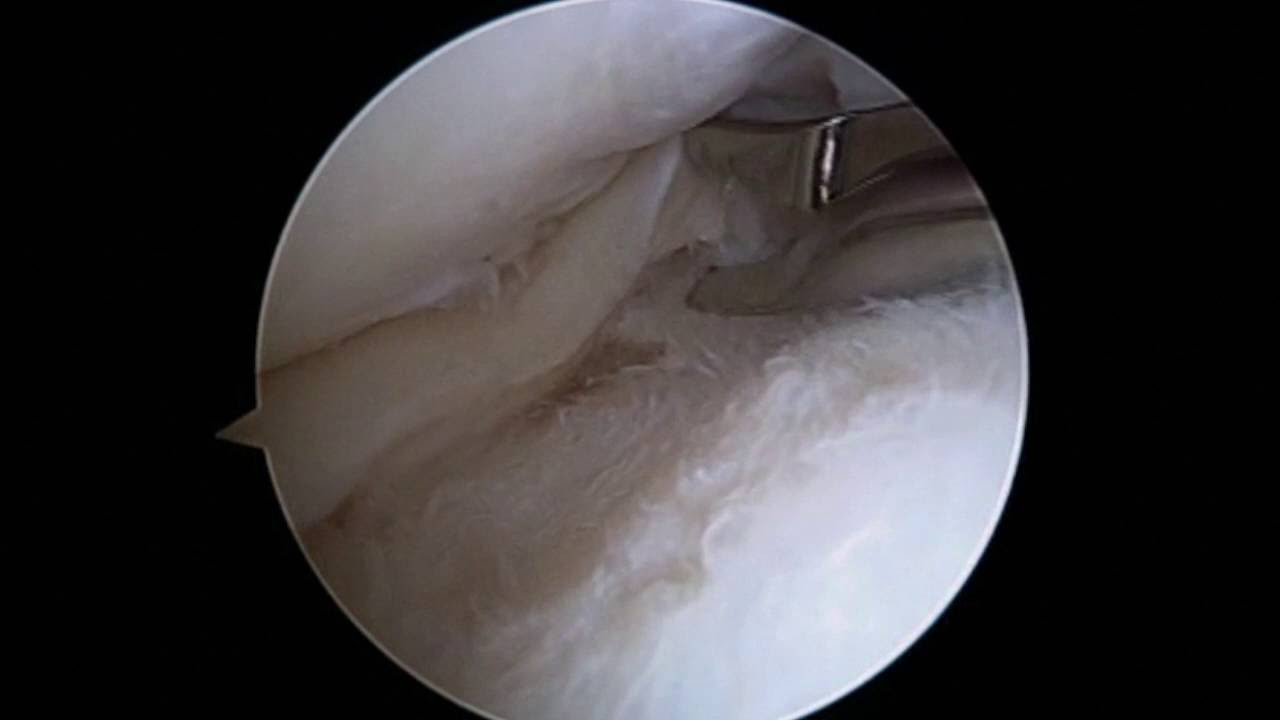

Partial Meniscectomy of a Bucket Handle Medial Meniscus Tear